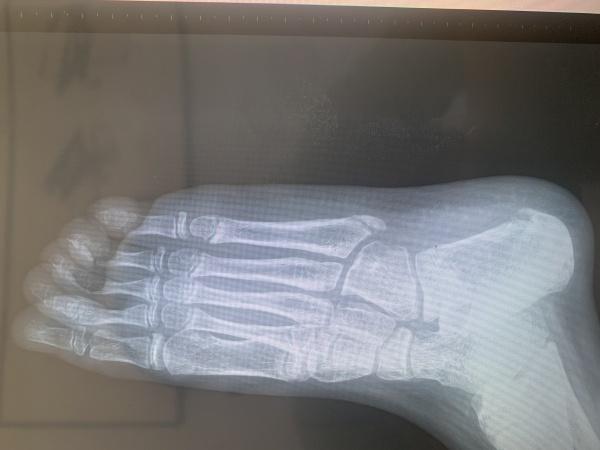

九岁儿童第5跖骨基底部各位大神帮忙看一下

发病一周 有没有手外伤孩子已经表达不清楚,本人考虑骨骺,以前没有遇见过想咨询一下各位大神,这种情况该如何恢复。儿童9岁

分明是右足,为什么会诊断为手外伤,第5跖骨基底部外侧为骨骺而已!

骨骺未愈合。。。。